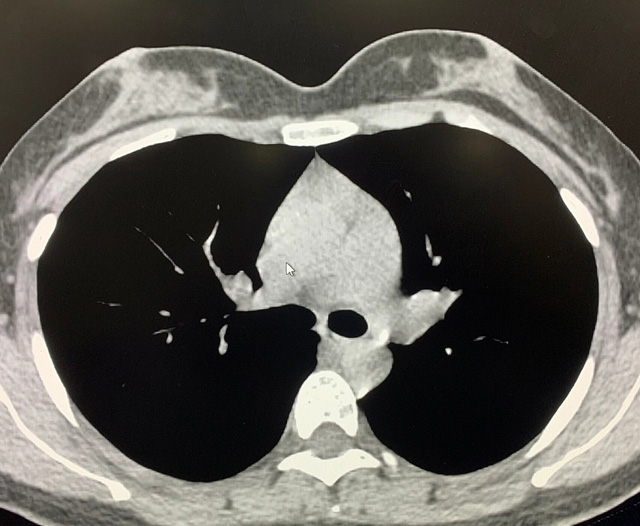

能谱纯化技术的核心是通过物理滤过(如锡滤片)或软件算法,选择性滤除低能X射线光子,保留高能光子。在胸部低剂量CT扫描中显著提升了图像质量与辐射剂量的平衡。

优势辐射剂量显著降低相较于常规CT,辐射剂量减少约70%-90%,尤其适合需多次随访的高危人群(如肺癌筛查),降低辐射相关癌症风险早期肺癌筛查效果明确可清晰检测毫米级肺结节,显著提高早期肺癌检出率,降低死亡率。检查快捷且普及性高单次扫描仅需数秒,无需对比剂,设备广泛配置于基层医院,便于大规模筛查。长期成本效益显著虽单次费用与常规CT相近,但早期干预可大幅降低晚期治疗费用及社会医疗负担。技术优化提升图像质量迭代重建算法(如ASIR、MBIR)在降低剂量同时减少噪声,平衡影像质量与安全性。